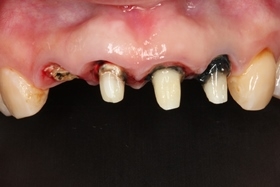

手術後,植體順利的植入預設的位置

當天拔牙,且立即植牙。

手術後,植體順利的植入預設的位置。